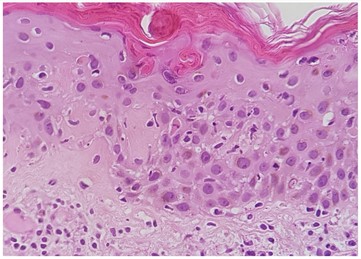

O estudo analítico (incluindo os autoanticorpos) e o exame micológico foram negativos. O exame histológico de pele revelou epiderme com paraqueratose, queratinócitos apoptóticos basais dispersos, epidermotropismo e degenerescência hidrópica basal; na derme observou-se infiltrado linfocitário perivascular sem eosinófilos e incontinência pigmentar (Fig. 3). A imunofluorescência direta revelou depósito granular basal de C3. Estes achados eram compatíveis com LECS.

Figura 3: Exame histológico com paraqueratose, epidermotropismo, degenerescência hidrópica basal e infiltrado linfocitário perivascular sem eosinófilos.